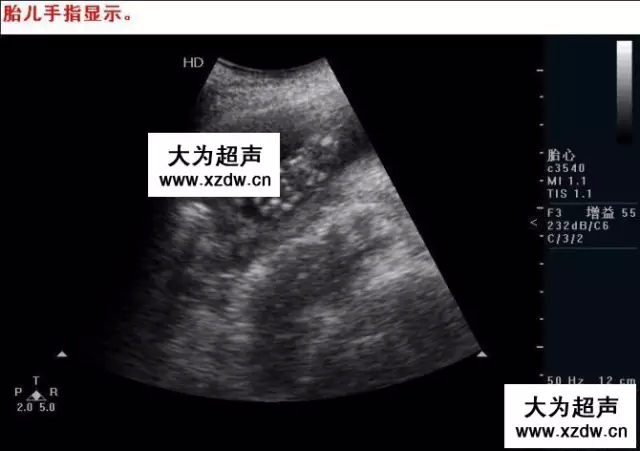

產(chǎn)科超聲正常圖片